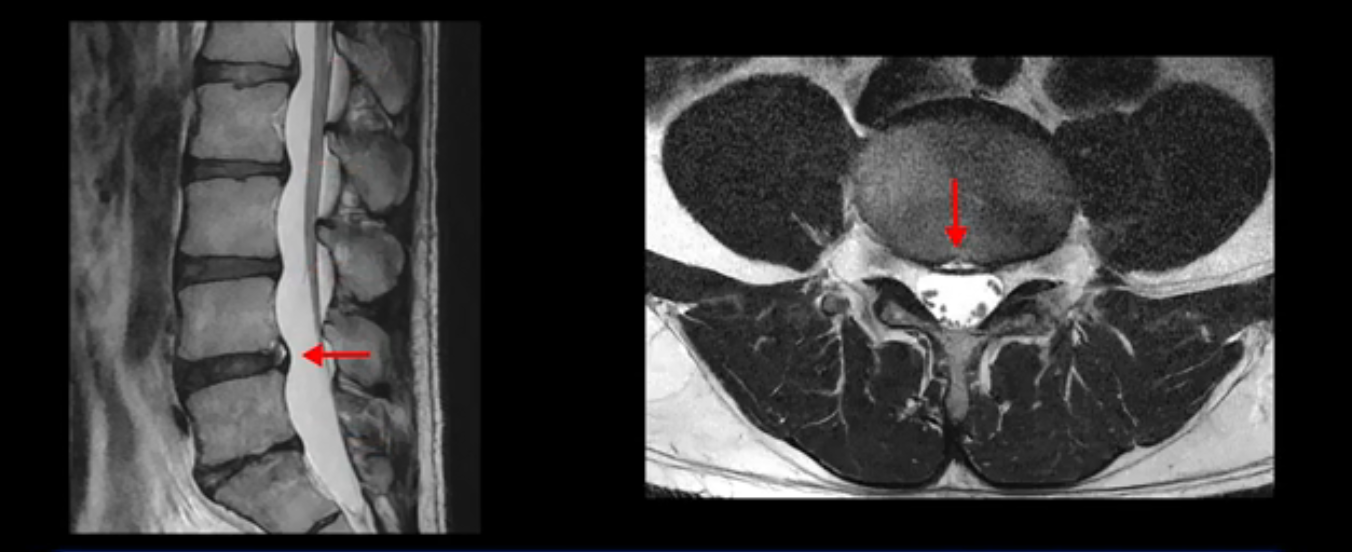

5번 1번 역시 가운데로 디스크 조금 밀려 나와있지만 신경 공간 넓이는 아주 넓어서 신경 눌림 있을 거라고 예상이 안됩니다.

추간공도 보시다시피 왼쪽, 오른쪽 전부 다 매우 넓어서 신경이 눌릴만한 부분이 전혀 보이지 않습니다.

앞서 1번 2번, 4번 5번, 5번 1번의 디스크가 찢어지고 조금 밀려 나온 게 최근에 찢어진 게 아니고 오래된 걸로 보인다고 말씀 드렸죠. 왜 그럴까요? 만약 급성으로 찢어진 것이라면 아주 심한 디스크성 통증이 있겠죠. 기침이나 재채기를 하면 심하게 아프고 허리를 조금만 구부리거나 비틀면 아주 날카로운 통증들이 생길 겁니다. 그런데 이분은 이런 증상이 전혀 아닙니다. 또 디스크의 밀려나온 정도도 전혀 심하지 않기 때문에 이분이 가지고 계신 양쪽 다리 저림, 특히 이분은 누워있을 때도 양쪽 발이 발가락까지 쑤신다고 하는데 이정도 디스크 때문에 그런 증상은 생길 수가 없는 겁니다. 이처럼 이분의 가벼운 디스크 탈출은 이미 오래 전에 진행되었고 섬유륜 자체는 이미 아문 상태인데도 디스크내장증을 진단받은 환자들 중에는 본인이 섬유륜 파열 환자라고 끝까지 믿는 분들이 많습니다. 다시 말하지만 디스크내장증이라는 진단을 받은 환자들을 보면 거의 전부 다 섬유륜 파열 증상이 아닙니다. 증상이 완전히 다릅니다. 진단이 애초에 잘못되면 어떤 치료를 받아도 좋아질 수 없습니다.

그럼 MRI를 자세히 봤으니까 이제 이 환자의 증상은 실제 왜 생기고 어떤 문제 때문에 아픈지에 대해서 차분히 설명을 드리도록 하겠습니다. 이 환자분의 진짜 통증의 원인은 무엇일까요? 이건 디스크의 문제가 아닙니다. 이 환자분의 진짜 통증의 원인은 허리의 기능이 완전히 무너진 겁니다. 허리의 기능 중에 가장 중요한 부분을 차지하는 게 근육인데, 이분의 근육 기능에는 오래 전부터 문제가 많았습니다. 이분은 작년에 앉지 못하고 양쪽 다리가 저리는 심각한 증상이 발생했는데요. 그런데 이런 증상이 발생하기 훨씬 이전부터 운동을 조금만 무리하면 허리가 뻐근하고 아픈 증상들이 있었습니다. 10년도 더 되는 오랜 기간 동안 허리가 조금씩 아프고 만성적으로 안 좋은 상태였는데, 6개월 전 어느 날 무리한 운동을 한 후에 허리와 근육의 기능적인 문제가 한계선을 넘어가니까 더 심한 증상들이 쏟아져 나오는 거죠.

허리 기능의 가장 중요한 부분이 허리를 지탱하는 건데, 우리 허리가 가장 부담을 받는 자세가 앉는 겁니다. 그래서 이렇게 허리 기능이 무너지고 망가진 환자들의 가장 중요한 첫 번째 증상이 앉지를 못하는 겁니다. 앉을 때 허리가 지탱을 해줘야 되는데 지탱을 하지 못하니까 허리나 엉덩이가 아프고 다리까지 저린 것이죠.